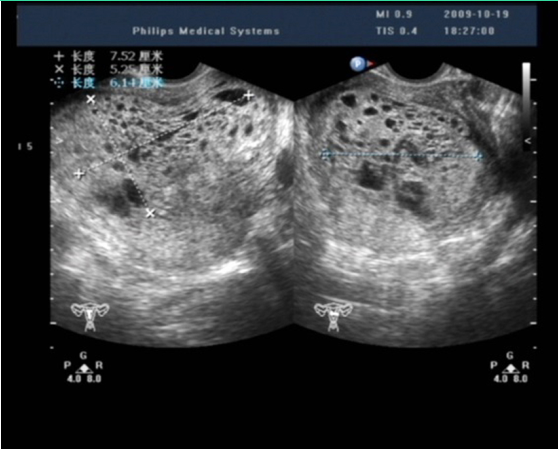

1.超声检查 是常用的辅助检查,最好采用经阴道彩色多普勒超声。完全性葡萄胎的典型超声图像为子官大于相应孕周,无妊娠囊或胎心搏动,宫腔内充满不均质密集状或短条状回声,呈“落雪状”,水泡较大时则呈“蜂窝状”。常可测到双側或一侧卵巢囊肿。彩色多普勒超声检查可见子宫动脉血流丰富,但子宫肌层内无血流或仅稀疏血流信号。部分性葡萄胎可在胎盘部位出现由局灶性水泡状胎块引起的超声图像改变,有时还可见胎儿或羊膜腔,胎儿通常畸形。早期葡萄胎妊娠的超声征象常不典型,容易误诊。

完全性葡萄胎超声影像(患者B)

子宫增大,宫腔内充满蜂窝状不均质回声,大小7.5cm×6.3cm×5.3cm,内见众多大小不等暗区